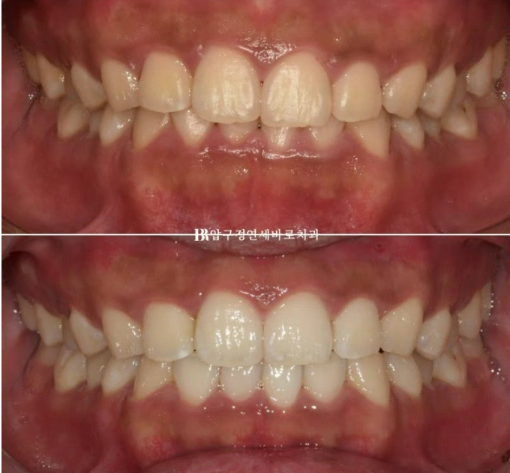

웃을 때 왼쪽 치아가 내려와 보인다라는 이유로 교정치료를 위해 찾아오신 환자분입니다.

윗니가 아랫니를 너무 많이 덮는 것을 과개교합 이라고 합니다.

아랫니는 거의 안 보입니다.

4개월 간 14개의 장치를 다 낀 후의 교합입니다.

파란 화살표 부위에 환자분이 고무줄을 열심히 걸어주었으며 4개월 간 교합평면 기울어짐, 과개교합은 잘 해결이 되었습니다

웃을 때 이제 더 이상 한쪽 치아가 내려와 보이지 않습니다.

결과도 좋고 환자분도 만족하여 재제작 없이 치료를 종료하기로 했습니다.

24.02~24.07

과개교합이 해소가 되면서 이제는 다물었을 때 아랫니도 보입니다.

압구정 인비절라인 라이트 4개월간의 변화입니다.

환자분의 훌륭한 협조도, 교정용 나사 미니스크류의 사용, 적절한 치료계획이 단기간에 좋은 결과를 만들었습니다.